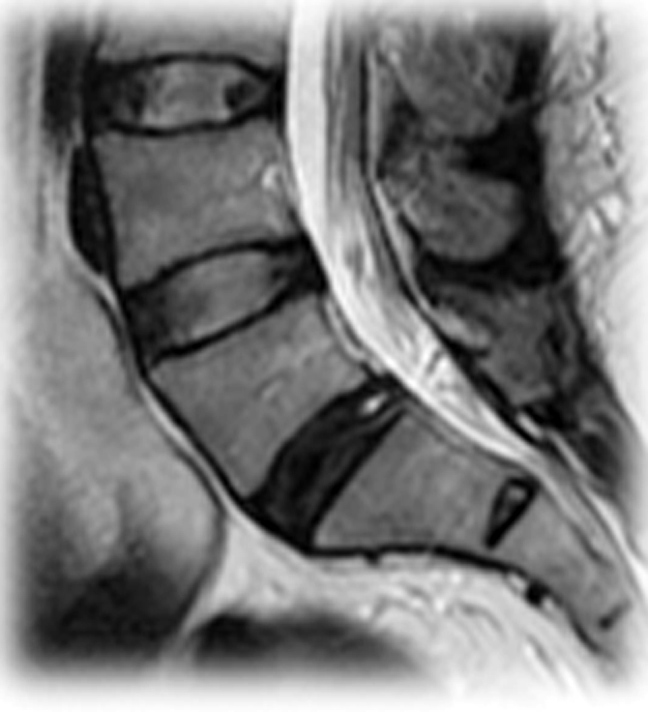

Στις συνήθεις περιπτώσεις ατελούς δισχιδούς ράχης επειδή οι οπίσθιοι σύνδεσμοι της σπονδυλικής στήλης σταματούν ψηλότερα, φαίνεται ότι δημιουργείται μια ανεπάρκεια στήριξης (αστάθεια) των τελευταίων δύο σπονδύλων (η δισχιδής ράχις αφορά τους τελευταίους δύο οσφυϊκούς σπονδύλους και τον πρώτο ιερό) με αποτέλεσμα να εμφανίζονται ως «μαύροι» δίσκοι στην μαγνητική τομογραφία.

Ο «μαύρος» δίσκος συνήθως εκφράζεται με χρόνια οσφυαλγία, χωρίς νευρολογικά ευρήματα.